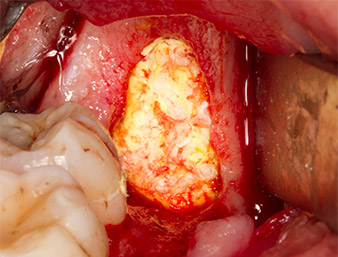

Subsequently, the autogenous bone tissue (Fig. 13) was placed into the alveole and the surrounding bone defect (Fig. 14). Collagen fleece covered the bone chips up to bone level as protection for the exposed nerve (Fig. 15). Sutures using vicryl thread, USP 4.0, were used to close the opened up soft tissue (Fig. 16). An Ibuprofen preparation (Seractil 400 mg, 3x1) and an antibiotic consisting of amoxicillin and clavulanic acid (Augmentin 1 g, 2x1) were prescribed postoperatively.

The wound healed without complications (Fig. 17) and the sutures were removed after seven days. The patient reported the return of proper sensitivity. There was no longer any pain.

apical portion of the alveole

Fig. 14: The apical portion of the alveole is covered with the autogenous tissue.

collagen fleece

Fig. 15: The defect is filled with collagen fleece up to bone level to protect the nerve. Bleeding initiates the healing phase.